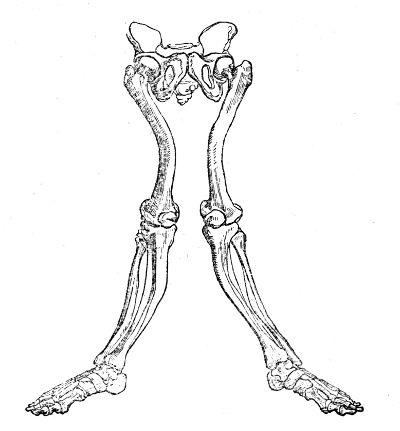

| Fractures of thePelvis and Lower Extremity | 574 |

| InjuLower Extremity | 600 |